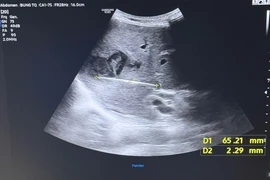

Em được chuyển khẩn cấp đến khoa Hồi sức cấp cứu, Bệnh viện Nhi Hải Dương. Khi vào viện, em ở ranh giới sinh – tử: Hôn mê sâu, ngưng tim; Rối loạn đông máu nặng, chảy máu phổi ồ ạt; Gan – thận – tim đều tổn thương nghiêm trọng; Các chỉ số sinh hóa cho thấy cơ thể gần như “sụp đổ”. Đây là một trong những tình huống nguy kịch nhất trong hồi sức sơ sinh.